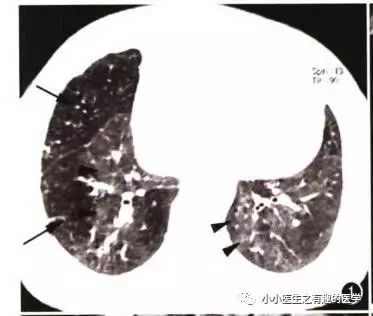

另外,CT发现肺纹理减少,也要警惕肺栓塞。先来说说马赛克。

马赛克征象:由于气道疾病或肺血管性疾病,引起相邻的肺区血液灌注上的差别而出现的不均匀肺密度区,称马赛克灌注。

以图说话,下面都是马赛克,关注了

如图:

假如CT平扫发现肺部某些地方血管稀疏,灌注不够,千万不要以为没事,有时候,就是肺栓塞,需要警惕。

马赛克,需要警惕肺栓塞,它是肺栓塞的间接表现。并且,在临床中,间断会遇到这样的情况。